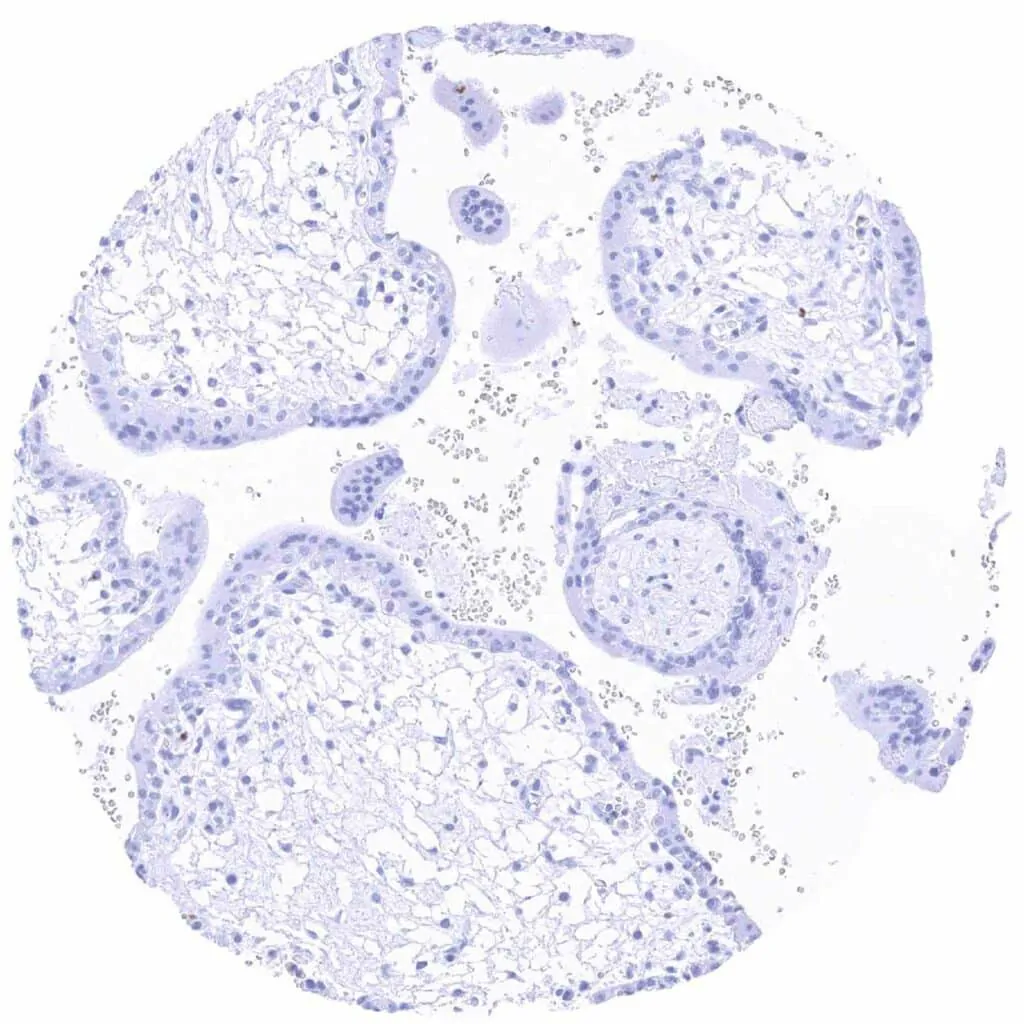

Placenta early, decidua (pregnancy)

Placenta early